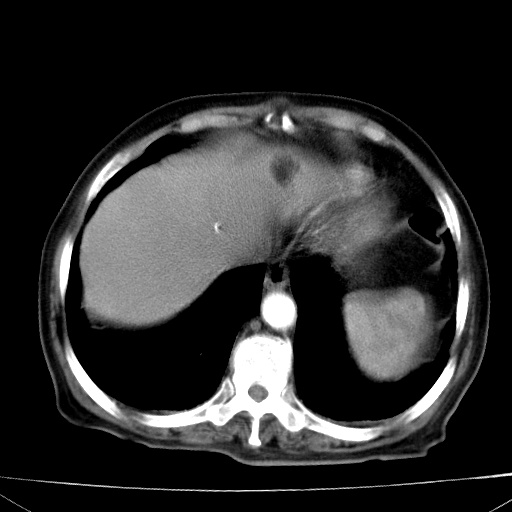

网站人气太旺!昨天的帖子就沉到海底,只好再发贴!ct18338:女 78岁,肝胆病变,已增强,再会诊!原帖链接:http://www.radida.com/bbs/forum.php?mod=viewthread&tid=50032

1)考虑胆囊癌侵犯肝脏并肝门区、腹膜后及右侧膈角后淋巴结转移。2)肝左叶近肝顶部囊肿。3)肝左叶肝内胆管结石。4)左肾近下极囊肿。